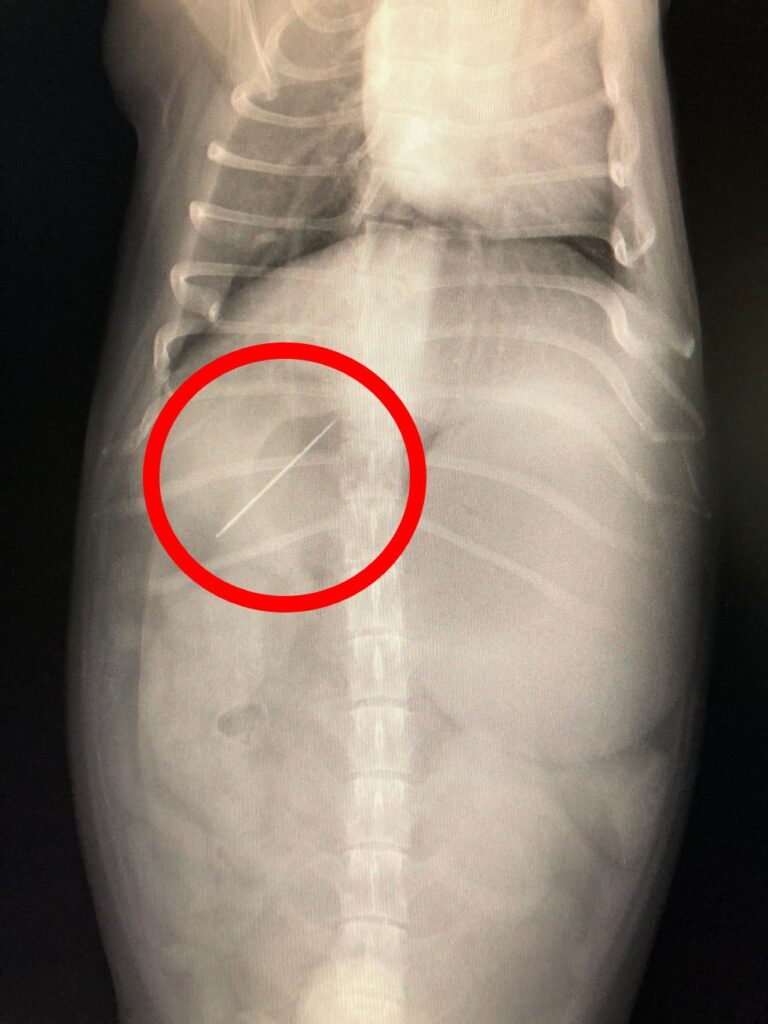

・レントゲン検査 異物の有無や腸の状態を確認 (異物内容によってはレントゲンにうつらないこともあります)

・造影レントゲン検査 (異物の位置やうっ滞、閉塞を確認)

・超音波検査 胃腸運動の停滞は見られないか、腸の形に問題がないか、炎症がないか、腹水など溜まっていないかどうかを確認